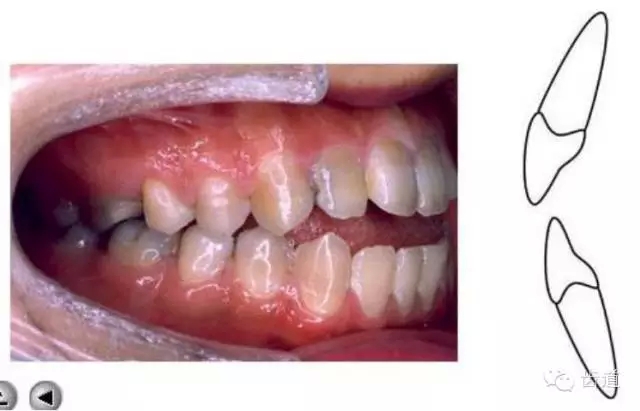

上下牙列間存在著覆蓋、覆牙合

覆蓋Overjet (the horizontal overlap)

覆牙合Overbite (the vertical overlap)

覆蓋(over jet,即超牙合):水平距離

覆牙合(over bite):垂直距離

覆牙合、覆蓋生理意義

a.保護(hù)唇頰舌軟組織

b.提高咀嚼效率